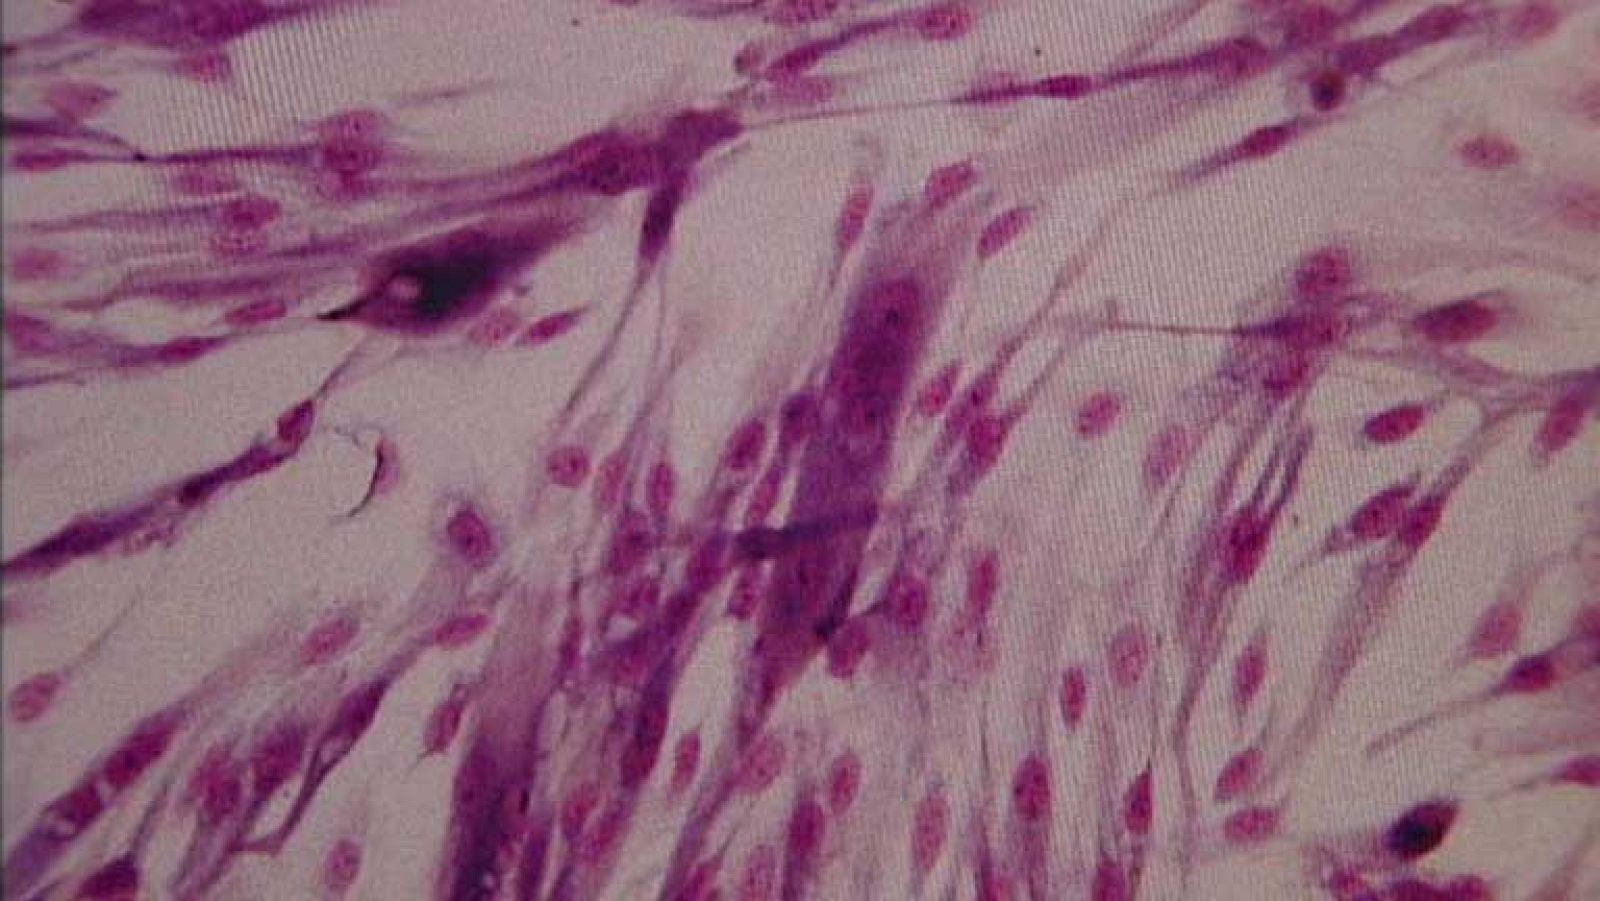

Avance científico contra el cáncer

Nuevo avance científico en la lucha contra el cáncer. Un grupo de científicos, entre ellos dos españoles, han descubierto por que algunas células...